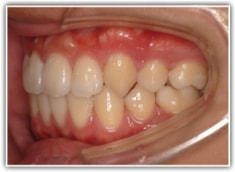

治療前

治療開始時

上下顎とも前突しており、叢生もあります。分析値からも抜歯対象症例です。